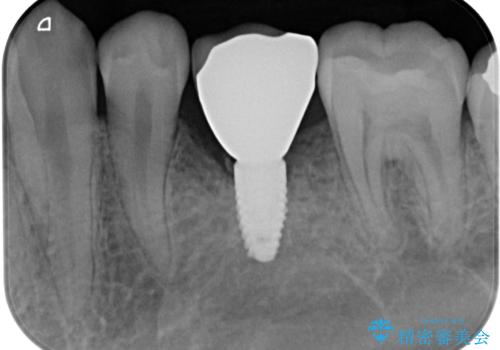

- 乳歯を抜歯したところにインプラントをしたいと来院された患者様です。

永久歯の先天欠如による乳歯の晩期残存があり、その乳歯が虫歯になってしまい保存不可能になり、他院で抜歯をし義歯を使用していた状態です。

義歯では嚙みづらいため、インプラントによる補綴をしていくこととしました。

義歯と違ってしっかり噛めるようになって食事がおいしくなったと満足していただけました。